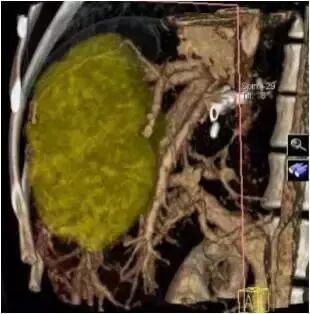

西门子双源CT(SOMATOM Drive)肿瘤分割技术可对肺、肝、淋巴结以及其它各部位组织病灶实施一键式自动分割 ,自动测量,并且提供多种重要的肿瘤学参数。为检查定性,手术、放化疗前后效果提供可靠依据。

西门子CT提供包括BF、BV、TTS、TTP在内的多种灌注参数及图像,为临床诊断肿瘤性质,早期评估手术效果提供诊断依据。